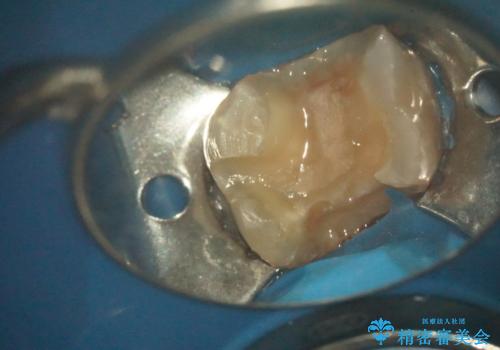

- 古い詰め物を除去し、腐ってしまった神経を顕微鏡下で丁寧に処理する

→根管治療完了後、土台を築造し、かぶせ物を製作してかみ合わせを回復する

すでに感染が根の先端まで及んでいたため、かなり強い痛みがありましたが、丁寧に根管治療をすることで内部を可及的に無菌化し、痛みが消失しました。